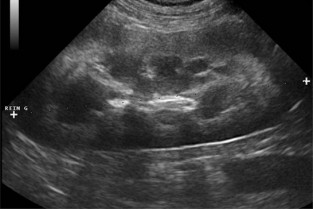

L’objectif du module central est d’instaurer un protocole standardisé pour l’examen échographique de l’abdomen. Les bases théoriques et pratiques de l’échographie, la topographie abdominale et l’aspect échographique normal des organes abdominaux seront également repris.

Les modules satellites se focalisent sur un appareil en particulier et permettent d’aborder l’aspect normal et lésionnel de chaque organe. L’intérêt et les indications de l’échographie interventionnelle sont également développés dans le module C.

- lister les principales indications et les limites de l’échographie dans l’exploration de l’appareil urinaire et de l’appareil génital

- réaliser un examen échographique de l’appareil urinaire et de l’appareil génital

- interpréter les principales images anormales décrites pour ces deux appareils.